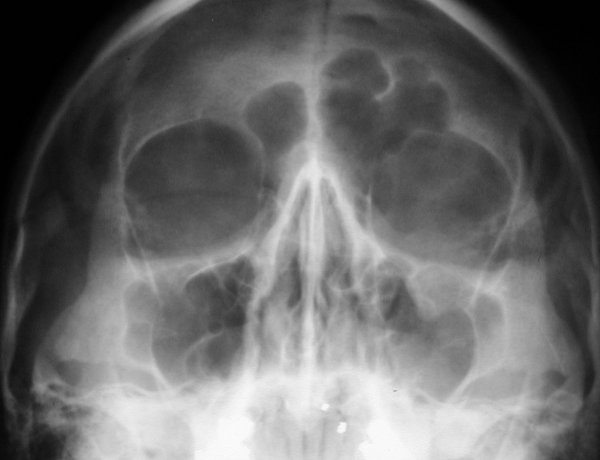

Return to Blowout Fracture